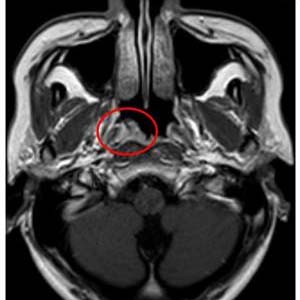

1.鼻咽癌:鼻咽癌是鼻咽部惡性腫瘤,由于腫瘤組織會刺激、破壞鼻咽部正常黏膜和組織,因此會出現鼻咽黏膜充血的現象,出現鼻涕帶血、鼻塞等癥狀。1.遺傳因素:鼻咽癌發病具有家族聚集性,如家族當中尤其是直系親屬當中有鼻咽癌患者,則后代的患病率響度來說會更高一點。

2.病毒感染:比較典型的就是EB病毒、冠狀病毒感染等,這些病毒會參與到鼻咽癌的發展過程當中,也就是說發生病毒感染未及時治療,也可能導致鼻咽癌問題。是一種常見的惡性腫瘤,其發生范圍很廣,比如80%以上的鼻咽癌患者在次檢測到淋巴結轉移。

隨著病情的發展,還會表現出與之相對應的臨床表現,比如:鼻咽癌會有回吸涕帶血,嚴重時會影響到顱神經,比如頭痛、上瞼下垂等,還會導致軟腭癱瘓,聲音嘶啞,伸舌偏斜等。鎳元素可促進亞硝胺誘發鼻咽癌,酒精和煙草、維生素缺乏、性激素失調都增加黏膜對致癌物的敏感性。